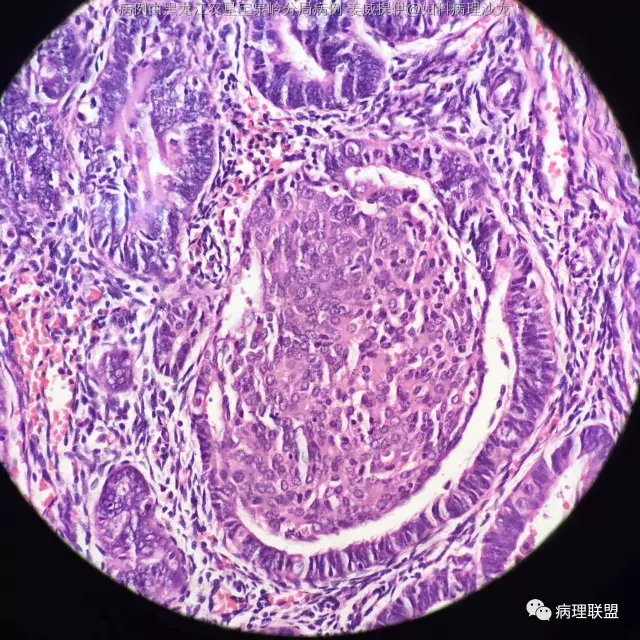

女 45岁,子宫内膜 全切子宫 术前非典(病例由黑龙江农垦宝泉岭分局病理 姜威提供,致谢!)

@黑龙江农垦宝泉岭分局病理 姜威 :子宫内膜样癌伴鳞状分化